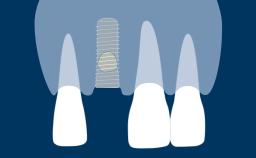

Este módulo concentra-se no conceito de integração de implantes dentários nos tecidos moles e duros da cavidade oral. A integração no osso é chamada de osseointegração e esse fenômeno, em específico, revolucionou essencialmente a maneira como os dentes ausentes podem ser substituídos. A osseointegração tem implicações clínicas para todas especialidades de dentistas envolvidas, bem como para pacientes com qualquer ausência de elementos dentários. Implantes são ancorados no tecido ósseo e penetram no tecido mole. É essencial entender os tecidos moles e duros ao redor de reabilitações sobre implantes dentários, pois somente isso permite reabilitações ideais.

- definir a integração dos implantes dentários aos tecidos duros e moles

- discutir como ocorre a integração dos tecidos ósseos ou a osseointegração

- discutir como ocorre a integração dos tecidos moles e diferenciá-la com a de dentes naturais